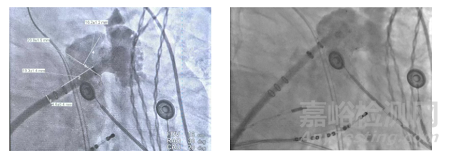

▲術(shù)前左心耳造影(左);封堵器展開(kāi)后TEE影像(右)

左心耳解剖:術(shù)中DSA 左心耳造影顯示,患者心耳形態(tài)為 “菜花狀雙分葉”,且存在 “縮口大 POUCH”(心耳開(kāi)口直徑 24mm,內(nèi)部腔室深度 25mm)—— 這類形態(tài)的風(fēng)險(xiǎn)在于傳統(tǒng)封堵器易出現(xiàn) “錨定不牢”(開(kāi)口窄導(dǎo)致器械固定差)或 “內(nèi)部漏血”(腔室大導(dǎo)致覆蓋不全)。

定位與釋放:通過(guò)3 個(gè) RO Marker 實(shí)時(shí)調(diào)整器械位置,確認(rèn)封堵器與心耳開(kāi)口同軸對(duì)齊后緩慢釋放;術(shù)后經(jīng) TEE 與 DSA 雙重評(píng)估,封堵器壓縮比為 15%(理想范圍 10%-20%),無(wú)瓣周漏,符合 PASS 原則。